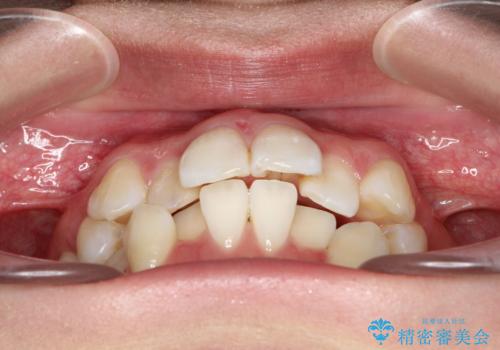

- 前歯のデコボコと上顎の前突感による口の閉じにくさを気にして来院された患者様です。

目立たない装置を希望されたので、上顎が裏側装置のハーフリンガルを選択し、上下左右の小臼歯(計4歯)を抜歯して矯正治療を行うこととしました。

期間はかかったものの、口元の張り出し感や歯のデコボコが解消され、患者様には大変満足していただけました。